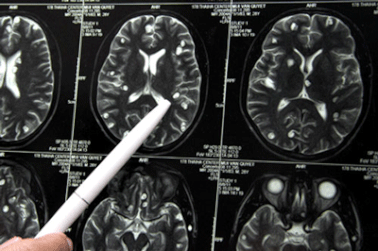

Sán làm tổ trong não vì 3 món nhiều người Việt thường ănChụp cộng hưởng từ sọ não thấy khối tổn thương ký sinh tại vùng não của bệnh nhân do ấu trùng sán dây lợn.

Liệt nửa người, đi khám mới biết sán làm tổ trong nãoĐau đầu, buồn nôn, sốt, tê liệt nửa người, ông S. được người nhà đưa đến bệnh viện. Kết quả kiểm tra cho thấy bệnh nhân có 5 ổ sán rải rác trong não, gây phù não. Đây chính là nguyên nhân dẫn tới các triệu chứng trên.